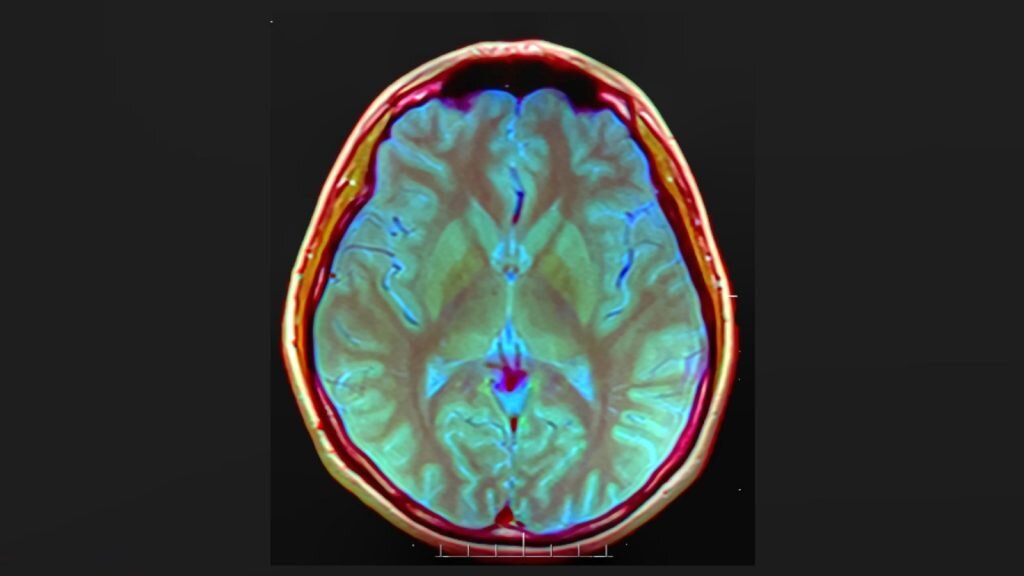

Загадки науки: изучаем паразиты мозга